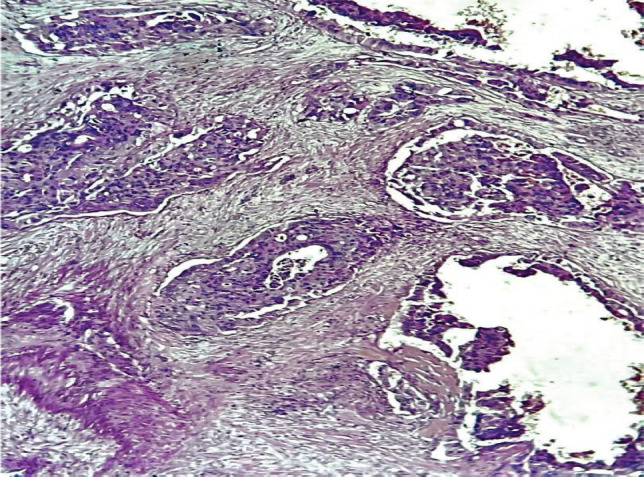

Upper urinary tract urothelial carcinomas (UTUCs) are rare malignant neoplasms, representing about 5% of all urothelial carcinomas (UCs). The incidence of primary UTUC in the renal pelvis and calyx is quite rare. UTUC is a high-grade tumour with a poor prognosis at presentation. Characteristically, UTUC presents with symptoms such as gross and microscopic hematuria or flank pain. Its mode of definitive diagnosis remains histopathology examination, despite using computed tomography urography (CTU) as the gold imaging standard. However, atypical clinical presentations and abnormal radiologic findings could lead to misdiagnosis of UTUC. We report a 59-year-old male who presented with recurrent left flank pain of 2 years duration, and an episode of hematuria. A CTU showed no classic radiologic feature of upper UCs; however, his abdominal magnetic resonance imaging was suggestive. He subsequently had a left radical nephroureterectomy. The post-operative histology report showed a primary invasive high-grade UC of the left renal pelvis and calyx. He was counseled on the findings and placed on surveillance. There are few reported cases of UTUC of the renal pelvis and renal calyx; given that it is a rare malignancy. This is quite concerning, especially with the missed imaging finding by CTU.